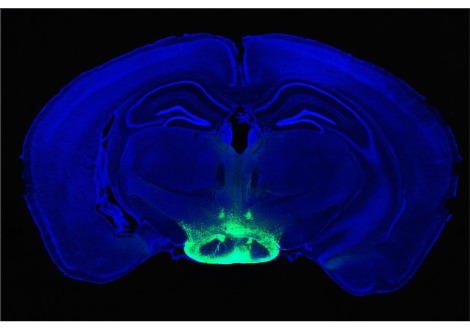

عندما تنخفض مستويات هرمون الاستروجين بعد الولادة، قد يلعب هرمون CCN3 دور تعزيز نشاط الخلايا الجذعية العظمية ، مما يؤدي إلى زيادة إنتاج الأنسجة ، حسبما ذكر الباحثون في 10 يوليو في مجلة Nature. ينشأ هذا الجزيء في منطقة ما تحت المهاد hypothalamus) ) ، وهي بنية الدماغ التي تساعد على تنظيم الشهية ودرجة حرارة الجسم . وإلى جانب احتمال حل لغز العظام القوية للأمهات المرضعات ، يمكن أن يشير هذا الاكتشاف أيضًا إلى طريقة لشفاء الكسور بشكل أفضل ومحاربة فقدان العظام في سن الشيخوخة .

في البحث الجديد، شرع العلماء في تحديد السبب الذي أدى إلى حجب مستقبلات هرمون الاستروجين في منطقة ما تحت المهاد في إناث الفئران ذات الكثافة العظمية العالية بشكل خاص . بالمقارنة مع الفئران الطبيعية ، فإن الفئران الطافرة "كان لديها عدد متزايد بشكل ملحوظ من الخلايا الجذعية العظمية"، كما يقول عالم بيولوجيا الخلايا الجذعية توماس أمبروسي من جامعة كاليفورنيا، ديفيس .